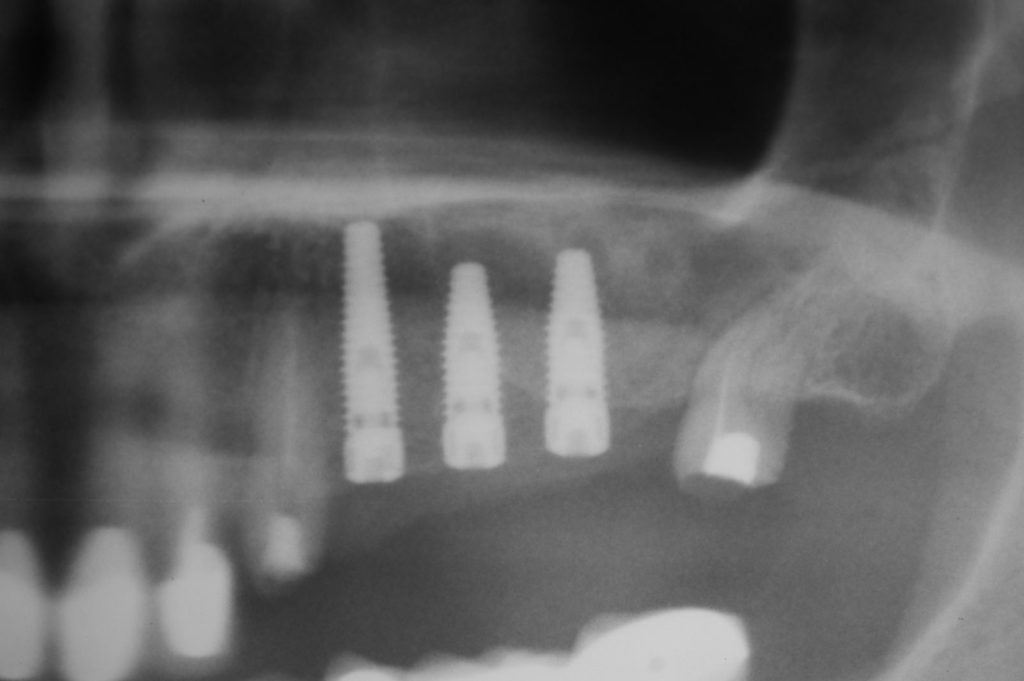

Przed podjęciem leczenia należy określić stopień zaniku kości szczęk oraz żuchwy. W tym celu przeprowadza się badanie kliniczne oraz odpowiednią diagnostykę obrazową pacjenta. Uwzględnia ona zdjęcie panoramiczne OPG jako podstawę dwuwymiarowego obrazowania podłoża kostnego oraz możliwe jest badanie tomograficzne CT lub bardziej precyzyjna tomografia stożkowa CBCT. Opcjonalnie wykorzystywana diagnostycznie tomografia pozwala na bardziej wnikliwą ocenę stopnia zaniku kości w trójwymiarowym, przestrzennym obrazie.

• Metoda otwarta – opisana w 1980 przez Jamesa i Boyna – polega na chirurgicznym dostępie do zatoki szczękowej poprzez jej boczną ścianę, następnie delikatnej preparacji, oddzieleniu wyściółki (błony Schneidera) bez jej perforacji, umieszczeniu pomiędzy nią a dnem zatoki materiału odbudowującego kość. Zabieg podniesienia dna zatoki szczękowej może przebiegać z jednoczesnym wszczepieniem implantów lub wszczepieniem ich w czasie odroczonym o 6–8 miesięcy. Warunkiem jednoczesnego wszczepienia implantów jest możliwość pierwotnie stabilnego ich umocowania w pozostałej własnej kości wyrostka zębodołowego. Najmniejsza jej ilość wg niektórych autorów to 1 mm.

• Metoda zamknięta – opisana w 1994 przez Summersa – bez szerokiego otwierania zatoki szczękowej, stosowana w sytuacjach wymagających niewielkiego zakresu rekonstrukcji na wysokość. W tej metodzie materiał regeneracyjny do odbudowy kości wprowadza się przez nawiercony kanał, komunikujący się z zatoką w pozycji zaplanowanej do wszczepienia implantu, lub tylko kondensuje się (zagęszcza, rozpycha i wydłuża) obszar kości dla uzyskania stosownej jej ilości i gęstości dla stabilnego umocowania implantu. Zabieg odbudowy kostnej wg Summersa wykonuje się przy użyciu specjalnego instrumentarium – zestawu osteotomów. Uzyskuje się dodatkowo 2–4 mm kości na wysokość

Zabiegiem, który rozwiązuje ten problem, jest podniesienie dna zatoki szczękowej, czyli odbudowa kostna w okolicy zębów trzonowych. Ubytek kości uzupełniany jest materiałem kościotwórczym, który układany jest pod błoną wyścielającą zatokę szczękową, zwaną membraną Schneidera. Zmniejszając objętość zatoki szczękowej, tworzy się tym samym stabilną strukturę kostną, umożliwiającą zabieg implantacji wszczepów śródkostnych.

Zatoki szczękowe to symetrycznie umieszczone w kościach szczęk przestrzenie powietrzne, posiadające komunikację z jamą nosa. Średnio pojemność zatok wynosi 24 cm3, a ściany wyścielone są błoną śluzową (membrana Schneidera). Dno zatoki szczękowej stanowi wyrostek zębodołowy, w którym umieszczone są zęby, często zlokalizowane tuż pod cienką wyściółką zatoki. Statystycznie najwęższy obszar kostny w tej strefie zlokalizowany jest na wysokości zębodołów pierwszego i drugiego zęba trzonowego.